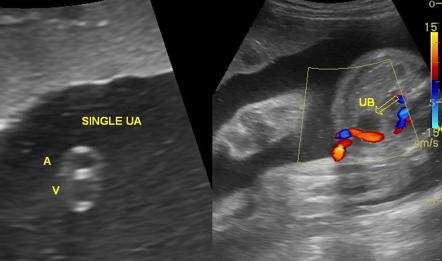

Hình ảnh dây rốn bình thường: 1 tĩnh mạch lớn (màu xanh) và 2 động mạch nhỏ (màu đỏ)

Hình ảnh dây rốn 2 mạch máu: 1 động mạch, 1 tĩnh mạch